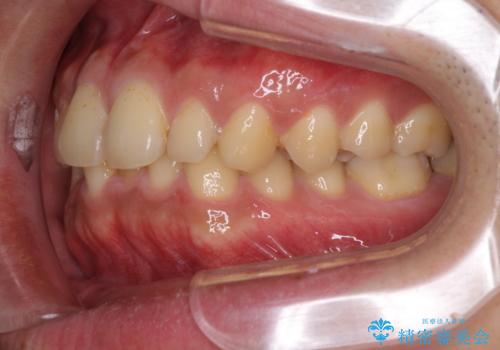

- 上下前歯のデコボコと下の前歯が隠れるほどの深い咬み合わせを気にして来院された患者様です。

インビザラインによる上下歯列の拡大と、IPR(歯と歯の間を削る)にるスペースの獲得により、口元のデコボコとディープバイトを改善することとしました。

デコボコがなくなったことで日頃の清掃が行いやすくなり、深い咬み合わせが改善したことで、食いしばりによる顎の負担も軽減されました。